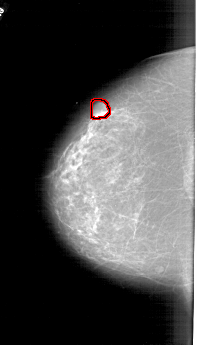

FILE: A_1778_1.LEFT_MLO.OVERLAY

TOTAL_ABNORMALITIES 1

ABNORMALITY 1

LESION_TYPE MASS SHAPE LOBULATED MARGINS CIRCUMSCRIBED

ASSESSMENT 4

SUBTLETY 5

PATHOLOGY BENIGN

TOTAL_OUTLINES 1

BOUNDARY